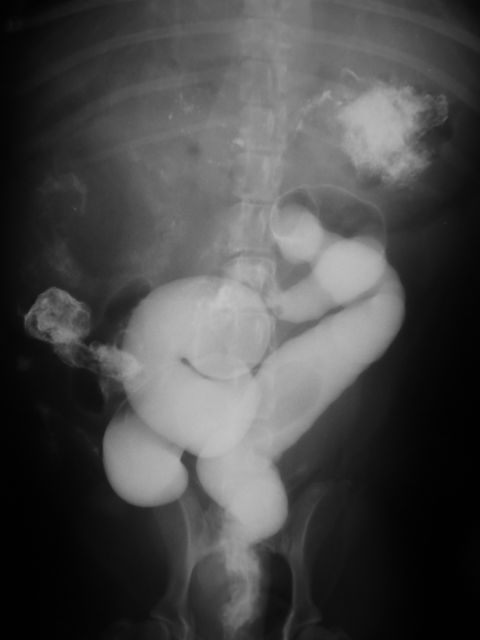

消化管造影検査↓

胃と小腸に造影剤の残存像が認められます。(造影開始から24時間後)手術を行うと異物は胃内と小腸内にありそれが糸状のもので繋がっておりました。

異物のなかでも紐状の異物は厄介で、通常のX-rayではまず写ってきません。また、小腸内にある異物は内視鏡などではとることが不可能なことが多いです。今回エコー検査にて紐状異物らしい所見は得れたのですが、開腹してからの確認でしか分からないことが多いです。動物の誤食による事故は多いので注意が必要です。